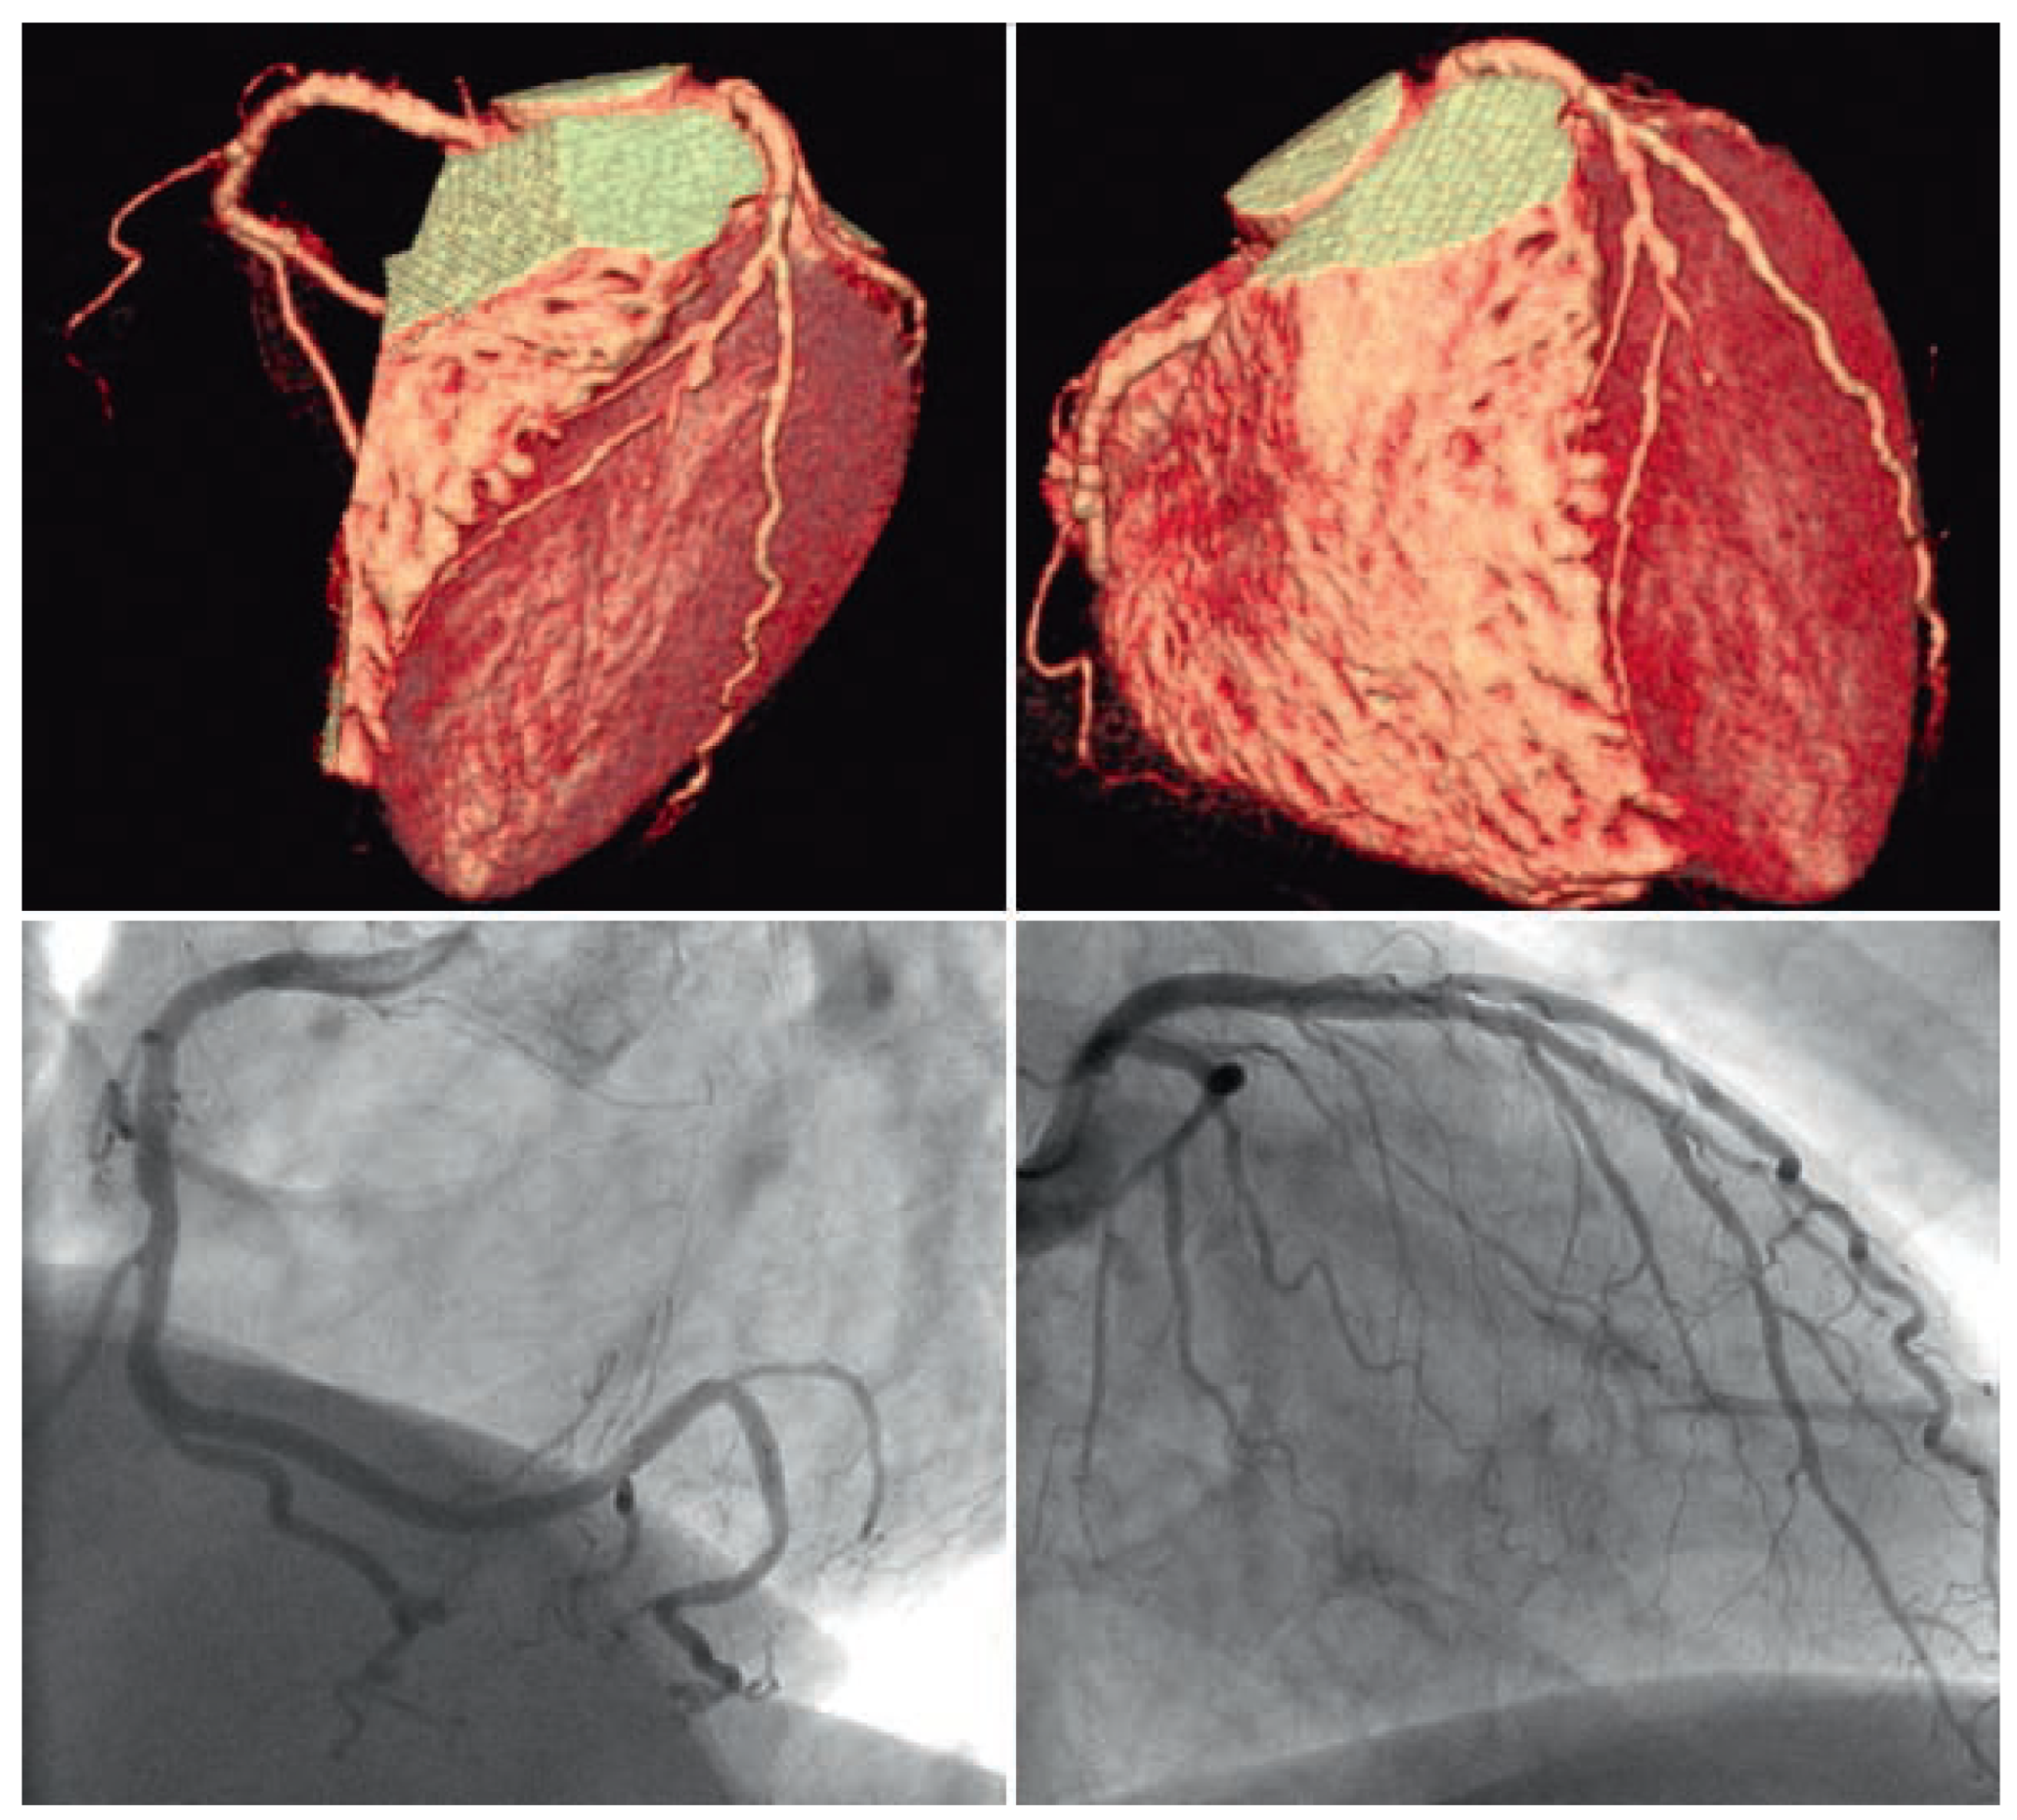

The industry once launched was unstoppable. First 4-slice CT angiography ensued, then 16-slice, then 64-slice, now 256-slice or double source, and this is not the end. The relief depictions of the coronary tree conjuring up 3-dimensionality were true eye catchers. Easily people were distracted from the fact that only the main vessels were seen, artefacts abounded, the lumen (what really keeps the patients alive) was less conspicuously seen, and finally, angiography could rival CT in terms of plasticity and colour (Figure 2) but did not have to because it had better things to offer.

The main advantage of angiography consists in the fact that it projects the entire heart onto a plane, thereby lossless reducing 3 dimensions to 2 dimensions. Every picture point is placed in an analogue fashion. Its position is therefore unaltered and genuine. Computerised pictures, be they from CT or magnetic resonance (MR) are also 2-dimensional. Yet, they are recalculated from a number of slices (0.5 mm) cut through the object. As the picture should be real-time or at least close to, powerful computers are required. On one hand, they can add a 3-dimensional flair to the picture; on the other hand, they are bound to miscalculate and creating pixel displacements or even gross artefacts. Figure 3 depicts, what happens, when a CT shows what is not really there which is rather the rule than the exception.

Figure 2. Tight lesion (arrow) in the left coronary artery shown by traditional angiography (insert) and 3-dimensional reconstruction using conventional modern X-ray equipment.